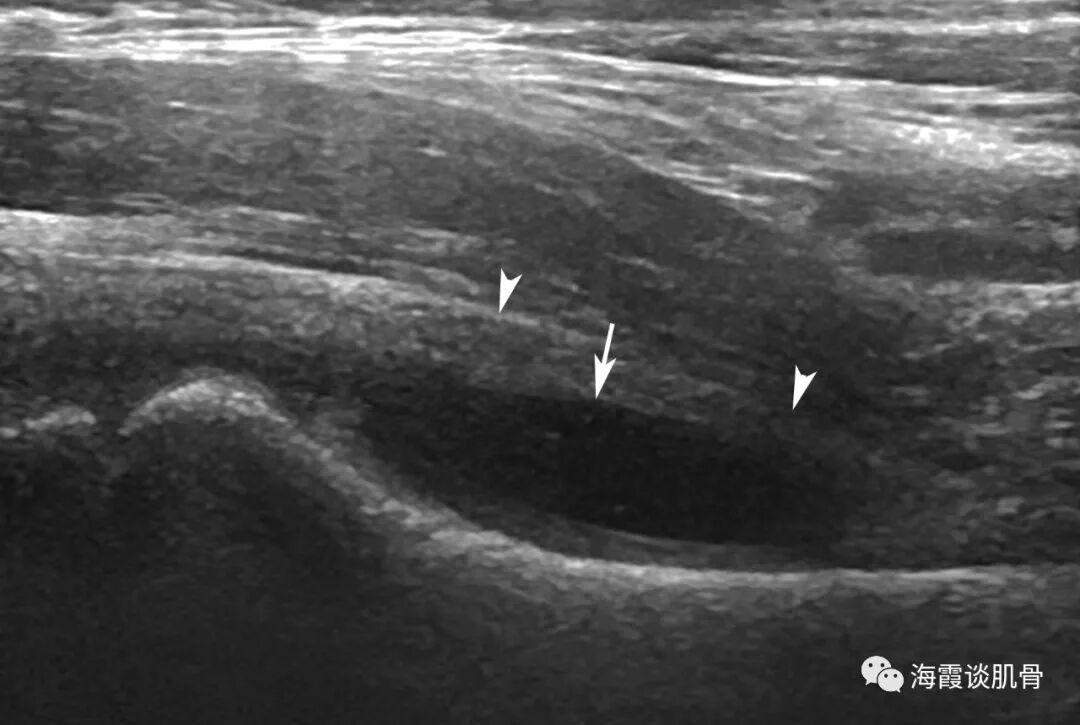

髋关节囊正常声像图:

(1)小儿髋关节前隐窝可有积液,但是一般<2mm。

(2)关节囊厚度<6mm。

(3)关节囊形态与股骨颈走形一致,向内微凹,。

图一:正常声像图,粗线为关节囊厚度,细线为积液深度,箭:关节囊形态,与深方股骨颈形态一致,向内微凹。